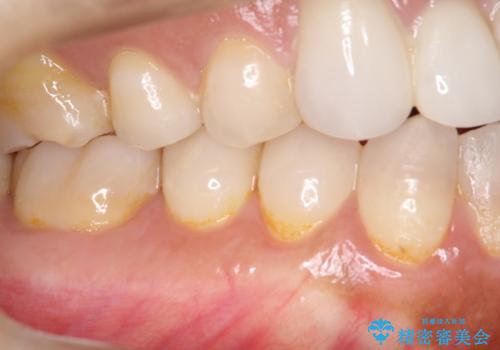

幸いなことに術後の痛みがほとんどなく、翌日には痛み止めも飲まずに済んだとのことでした。

治癒経過も良好で、患者様も満足されていました。また、知覚過敏も減ったとの事でした。